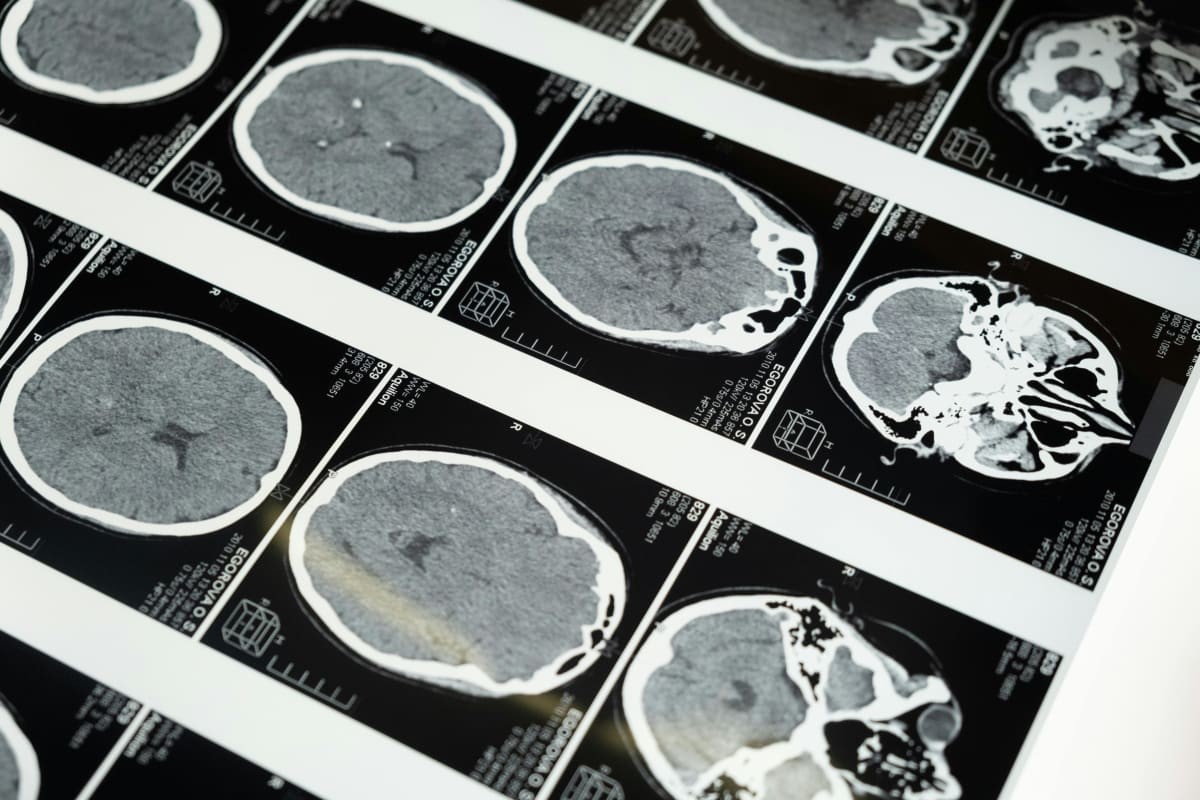

It all began while traveling in Poland with his wife, Katie Nicoll. One day, after hiking mountain trails, he woke up the next morning “not feeling quite right,” he told ABC News. “I had a brief phone call with my mum back in Tasmania. I don’t remember much after that. I know now I had a seizure.” After some tests in the hospital, Professor Scolyer was diagnosed with glioblastoma IDH wild-type.

According to the Brain Tumour Charity, glioblastoma is a type of brain cancer that is incredibly aggressive. Only 25% of those diagnosed live past the first year, and the five-year survival rate is only 5%.

Twelve days after he was given the immunotherapy drugs, Scolyer underwent surgery to have his tumor removed. Then several tests were carried out to verify if the drugs had prompted any positive effect. The test results were nothing short of “phenomenal,” Long described.

They discovered that there was a tenfold increase in the immune cells in the tumor, that they were activated against the cancer and they were bound to the drug. “Proving something that we’d already shown in melanoma, that there is no blood-brain barrier and historically conceptualized, preventing the drugs from reaching the tumor,” Long said, and added, “We could not have hoped for better results.”